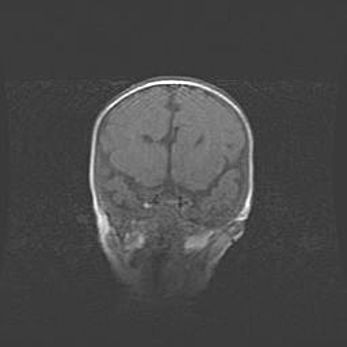

Открытая гидроцефалия.

Возраст: 9 месяцев 12 дней

Вес: 6800 г

Пол: мужской

Окружность головы: 41,5 см

Срок гестации: 28 недель

Гидроцефалия головного мозга у новорожденных имеет характерный признак: опережающий рост окружности головы приводит к визуально хорошо определяемой гидроцефальной форме сильно увеличенного в объёме черепа. Детские неврологи определяют следующие симптомы гидроцефалии у грудничков: выбухающий напряжённый родничок, частое запрокидывание головы, смещение глазных яблок к низу.